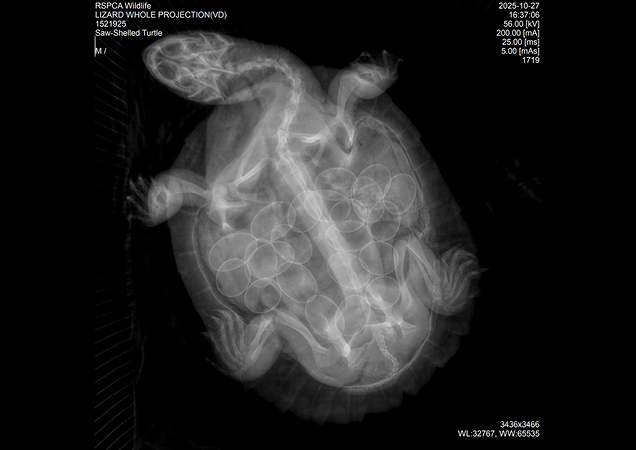

A radiograph revealed that this old mother was carrying 22 eggs!